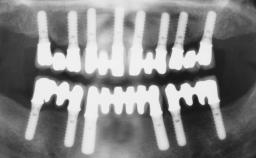

Conventional Loading of Six Implants in the Mandible and Final Restoration with a Full-Arch Metal-Ceramic FDP

A 68-year-old, completely edentulous male patient presented for evaluation and treatment options. He reported excellent general health and was taking no regular medication. He had been edentulous for approximately 12 years, having lost his teeth to periodontal disease and dental caries. The patient’s chief complaint was incompetent function. His secondary concerns included his appearance and the desire for a predictable outcome. He attributed his reduced functional capacity to his lower complete denture, which he described as poor. He was particularly concerned with the denture’s instability and poor fit. In general terms, he was satisfied with the maxillary complete prosthesis. The maxillary prosthesis was characterized by adequate retention, stability, and support, although the fit was considered less than ideal.

# of Implants 6

Defining Characteristics Fully edentulous lower jaw to be rehabilitated with two or more implants

Modality > 4 implants, extending to mental nerve region

Defining Characteristics Fully edentulous lower jaw to be rehabilitated with an implant-borne fixed dental prosthesis

Retention Screw-retained, with 4 or more splinted implants Screw-retained, with 4 or more splinted implants